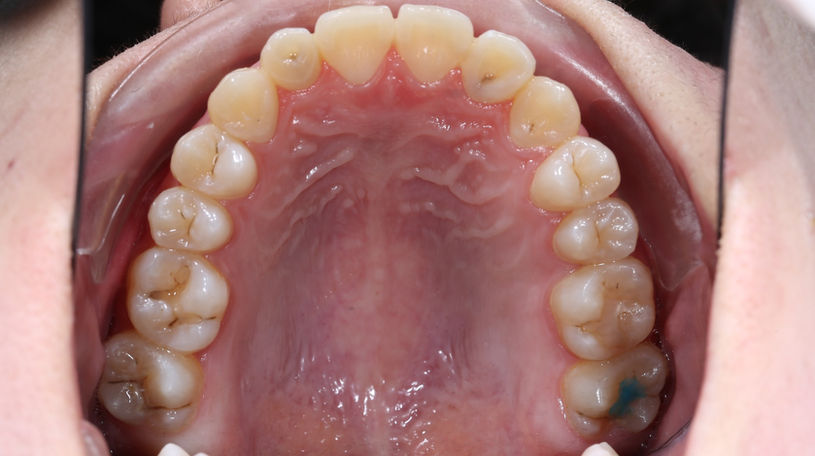

After

一般高中生年齡來找陳醫師做矯正的患者為數眾多,醫師會配合臉部外型、頭骨發育等基本面向先做評估,其次再針對牙齒排列與臉部的相對位置等問題進一步評估。下巴歪斜的清況每個人都會有,在不是非常明顯的情況前提下,將牙排列整齊的同時骨頭會稍微被調整一點;現在病患能夠很大方的開懷大笑、給予我們充滿自信的笑容!

此案例病患利用外側陶瓷美觀矯正器矯正治療,在唸書的年紀矯正,雖然忙碌辛苦一點,但甜美的果實總是在一番努力後更加鮮甜;患者與家長十分滿意治療的結果,樂心牙醫診所也為患者開心!